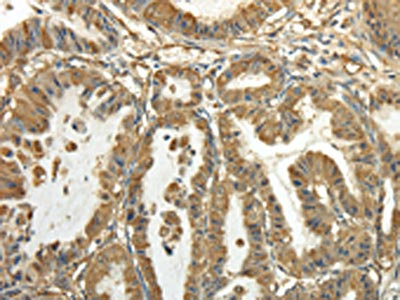

The image on the left is immunohistochemistry of paraffin-embedded Human prostate cancer tissue using CSB-PA162779(TUBA1C Antibody) at dilution 1/20, on the right is treated with fusion protein. (Original magnification: ×200)

The image on the left is immunohistochemistry of paraffin-embedded Human esophagus cancer tissue using CSB-PA162779(TUBA1C Antibody) at dilution 1/20, on the right is treated with fusion protein. (Original magnification: ×200)